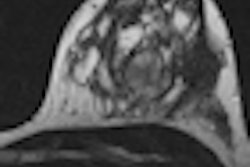

In a large prospective, multicenter trial, researchers found that the recently adopted BI-RADS categories for breast MRI work well in predicting which patients are most likely to have malignant lesions. Mass shape and contrast enhancement patterns were most predictive of cancerous lesions, according to a study published online May 15 in Radiology.

Mahoney and colleagues also found that lesion shape was a factor in malignancy. An irregular lesion shape had the greatest positive predictive value for cancer at 30%, while an oval-shaped abnormality had the lowest positive predictive value for cancer at just 5%.

As for mass margins, irregular margins at 20% and spiculated or jagged-edged margins at 33% had the highest positive predictive values for cancer. The lowest positive predictive values were found among smooth margins, at 5% positive predictive value.

In addition, masses with significant internal enhancement were most likely to be predictive of cancer, with a positive predictive value of 23%, compared with masses with minimal or moderate internal enhancement. Nonmasslike enhancement was most likely to be malignant in cases of ductal enhancement, with a positive predictive value of 50%.